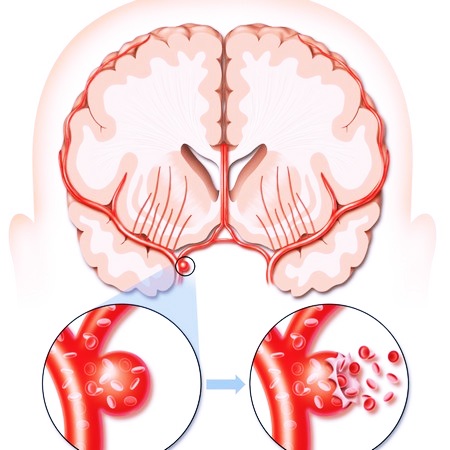

При геморрагической форме болезни стенка кровеносного сосуда разрывается, и кровь попадает в нервную ткань мозгового вещества. Все близлежащие клетки в области кровоизлияния сразу же гибнут, как и нейроны, получавшие кровь из разорвавшегося сосуда.

Разрыв сосуда вызывает рефлекторный спазм и сужение гладкой мускулатуры поврежденного сосуда и ближайших магистралей, что может способствовать прогрессу нарушения кровообращения и появлению новых симптомов патологии.

В отдельных случаях причиной инсульта становятся врожденные дефекты церебральных сосудов, при которых некоторых капилляров просто нет, и артерии напрямую переходят в вены. Такие аномалии могут приводить к образованию аневризмы – выпячиванию артериальной либо венозной стенки из-за ее истончения/растяжения. В результате подъема артериального давления или спазма сосудов эта стенка надрывается, и у человека случается инсульт или апоплексический удар.